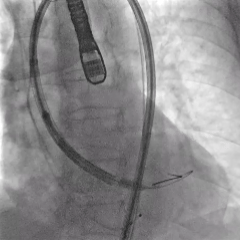

第二次瓣膜释放

造影评估,瓣膜位置可

右侧位造影,瓣膜深度可

多角度评估,瓣膜位置可,少量瓣周漏

脱钩后造影,瓣膜无位移,可见瓣周漏

20mm球囊后扩,瓣膜形态改善

后扩后评估,可见少量瓣周漏

最终瓣膜位置稳定